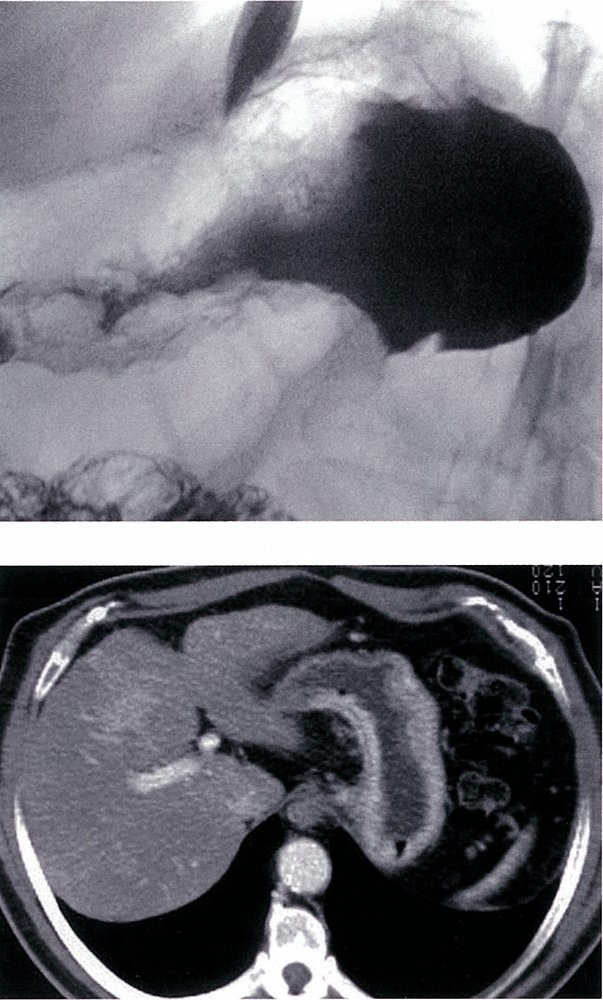

Ménétrier Disease

Hypertophic Gastropathy

(Menetrier Disease)

Foveolar Hyperplasia